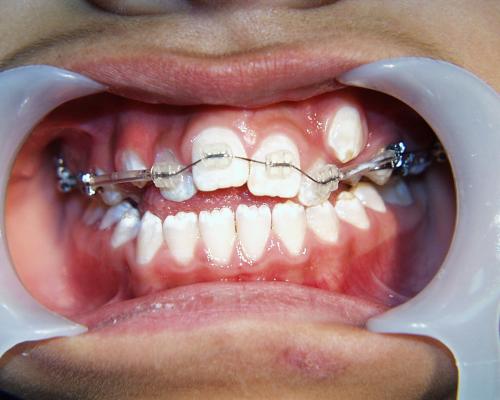

Während der Behandlung

Zunächst wurde der obere Zahnbogen geweitet und mit dem Ausrichten der Schneidezähne begonnen.

Die Zahnbogenmitte wurde eingestellt, die oberen Eckzähne eingeordnet und nach Einbeziehung des unteren Zahnbogens der offene Biß beseitigt.